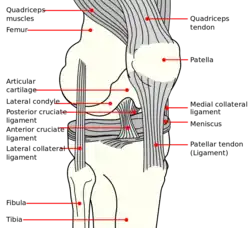

Knee diagram

Knee diagram Right knee-joint, from the front, showing interior ligaments.